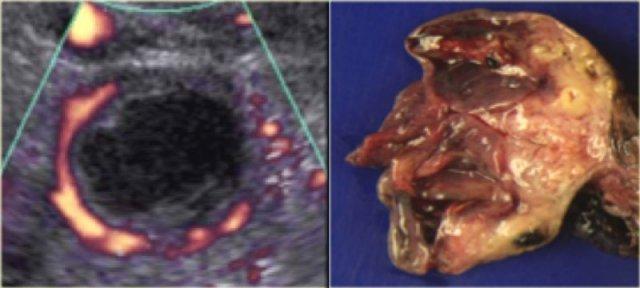

Nang hoàng thể trên MRI: hình ảnh chuỗi xung T2W mặt cắt ngang cho thấy nang hoàng thể đang thoái triển (mũi tên).

Đây là hình ảnh bình thường.

Buồng trứng phải cũng bình thường.

Siêu âm đường âm đạo cho thấy tổn thương dạng nang giảm âm kích thước lớn với các echo mức độ thấp lan tỏa

Lạc nội mạc tử cung dạng nang (Endometrioma)

Lạc nội mạc tử cung dạng nang (endometrioma) là loại nang hình thành khi mô nội mạc tử cung phát triển trong buồng trứng.

Bệnh ảnh hưởng đến phụ nữ trong độ tuổi sinh sản và có thể gây đau vùng chậu mạn tính liên quan đến chu kỳ kinh nguyệt.

Buồng trứng bị tổn thương ở khoảng 75% bệnh nhân mắc lạc nội mạc tử cung.

Trên siêu âm, hình ảnh endometrioma có thể đa dạng, nhưng đại đa số (khoảng 95%) bệnh nhân biểu hiện hình ảnh điển hình là nang đồng nhất, giảm âm với các echo mức độ thấp lan tỏa.